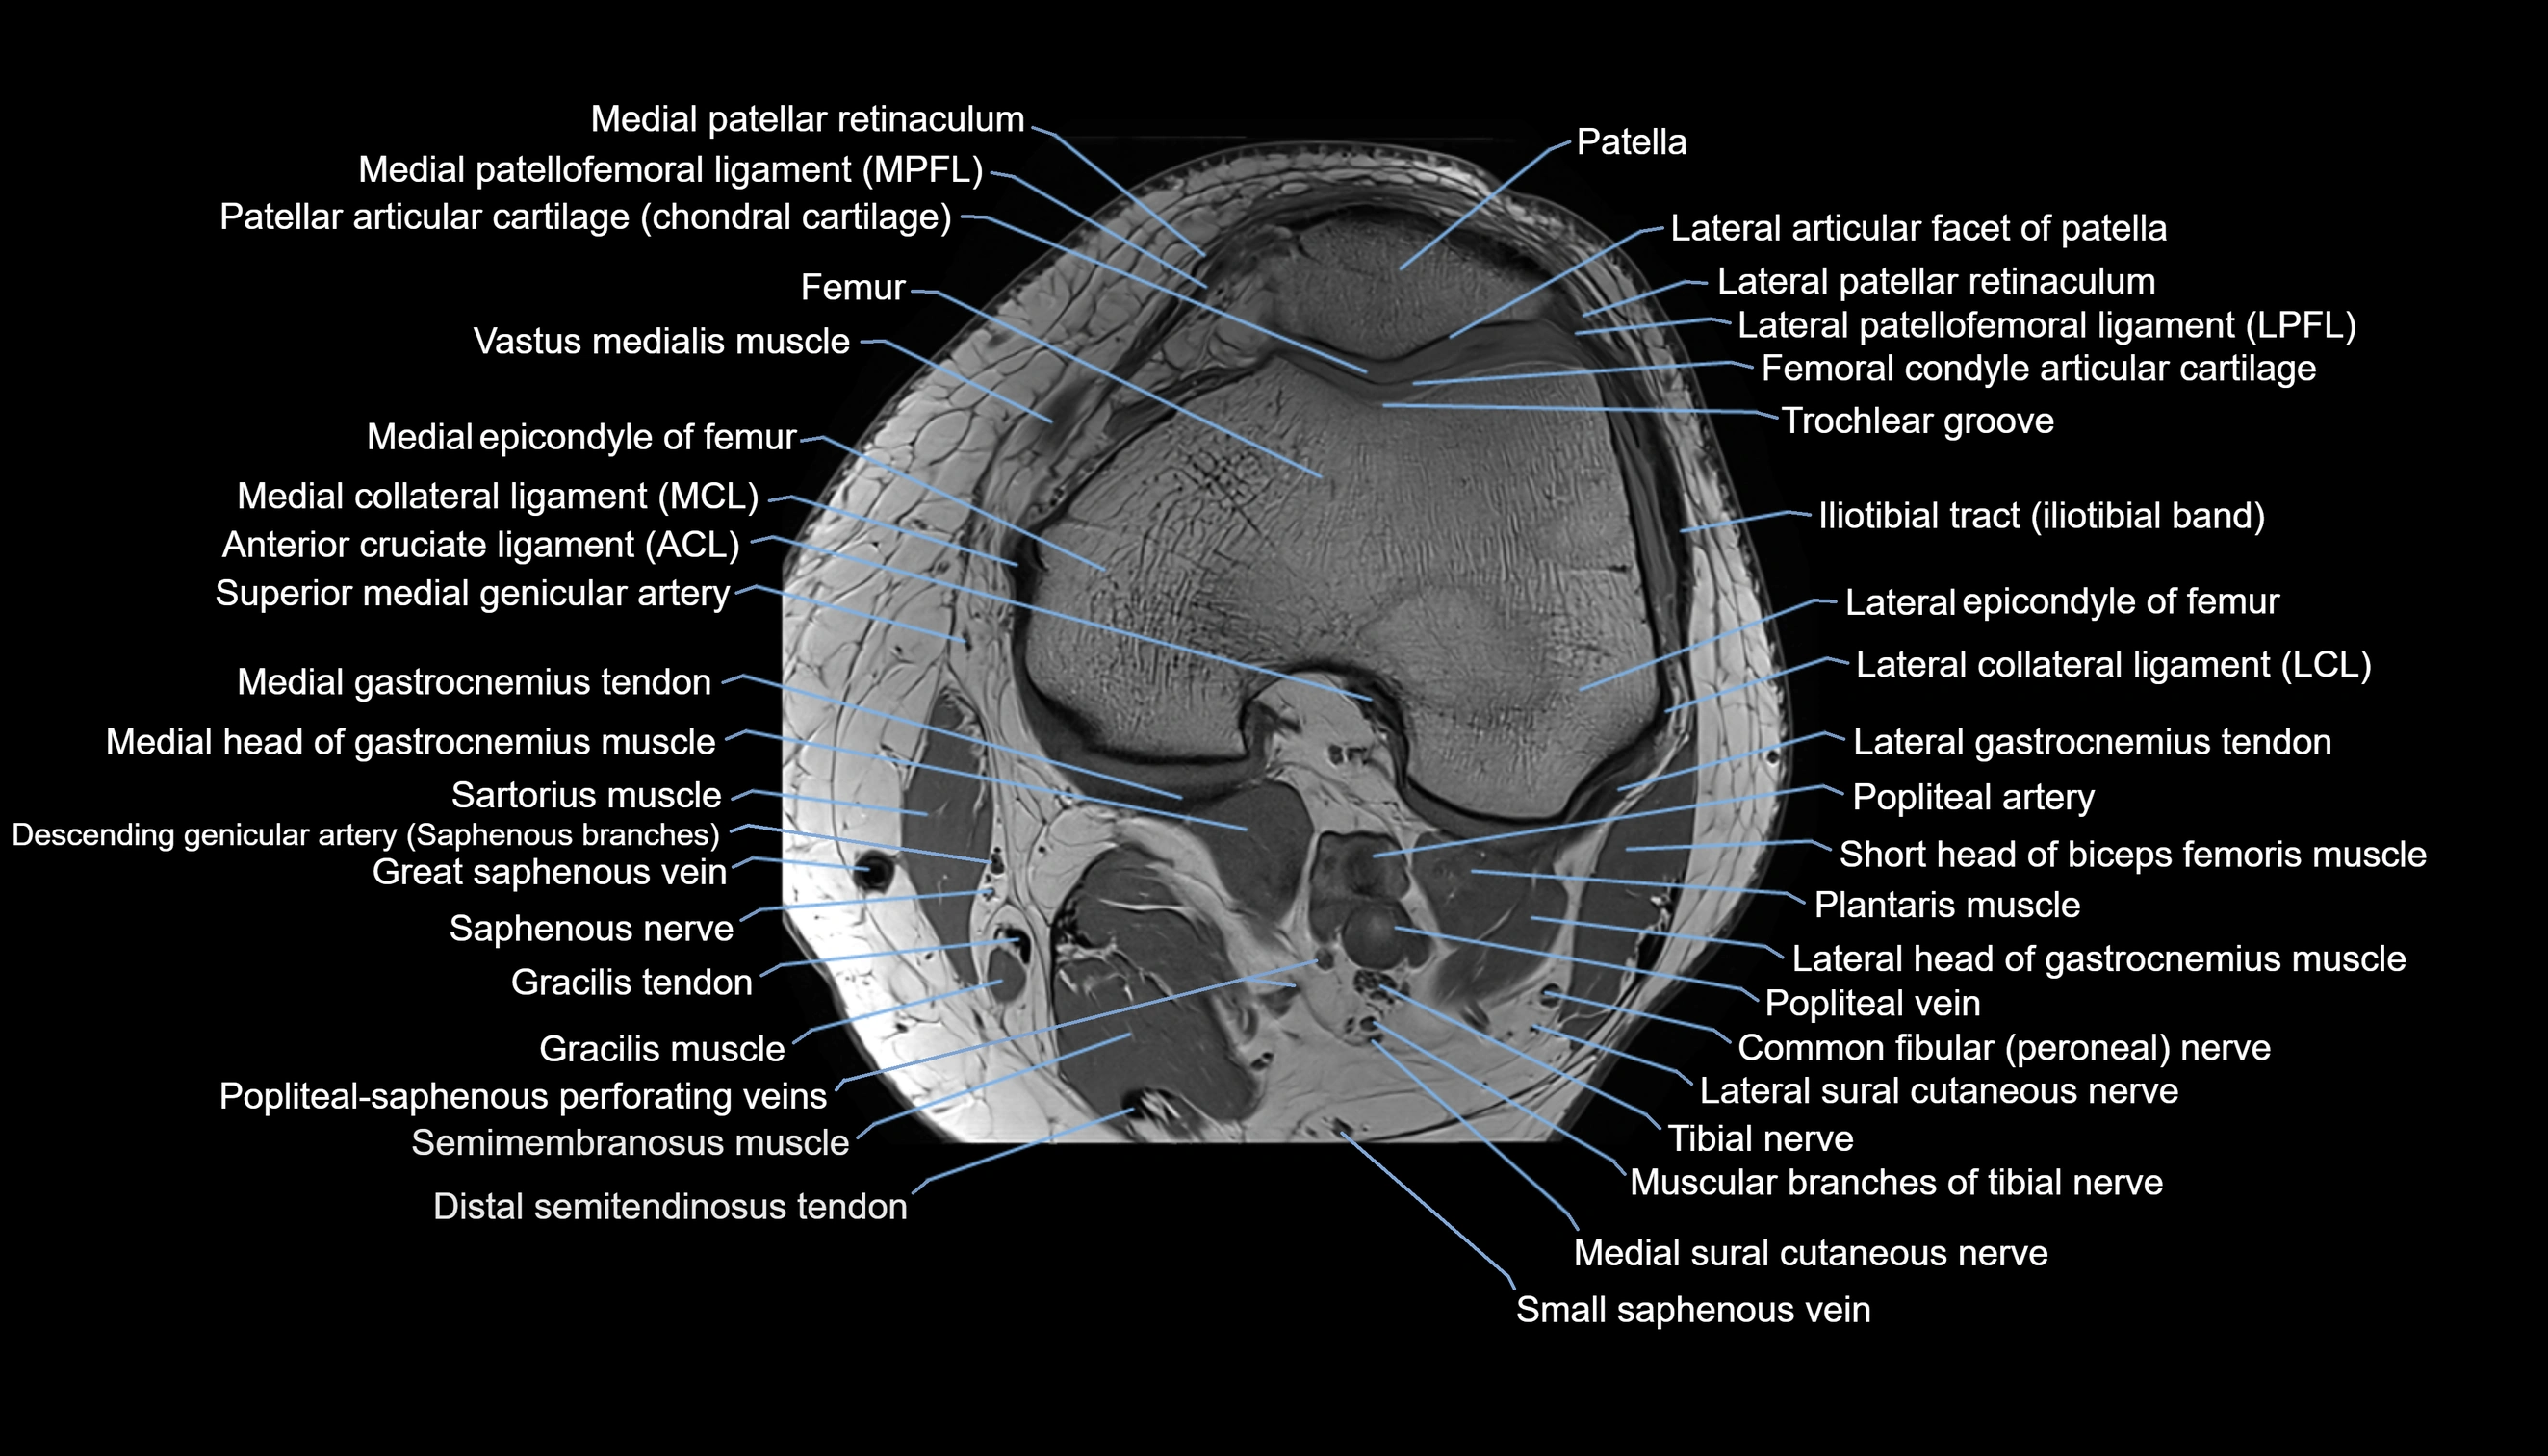

- Anterior cruciate ligament

- Common fibular nerve

- Gracilis tendon (Distal)

- Lateral collateral ligament

- Lateral epicondyle of femur

- Lateral gastrocnemius tendon

- Lateral head of gastrocnemius muscle

- Lateral patellar retinaculum

- Lateral patellofemoral ligament

- Lateral sural cutaneous nerve

- Medial collateral ligament

- Medial epicondyle of femur

- Medial gastrocnemius tendon

- Medial head of gastrocnemius muscle

- Medial patellar retinaculum

- Medial patellofemoral ligament

- Medial sural cutaneous nerve

- Patella

- Patellar articular cartilage

- Popliteal artery

- Popliteal vein

- Popliteal–Saphenous perforating veins

- Sartorius muscle

- Semimembranosus muscle

- Semitendinosus muscle

- Small saphenous vein

- Tibial nerve

- Trochlear groove

- Vastus medialis muscle

- great saphenous vein